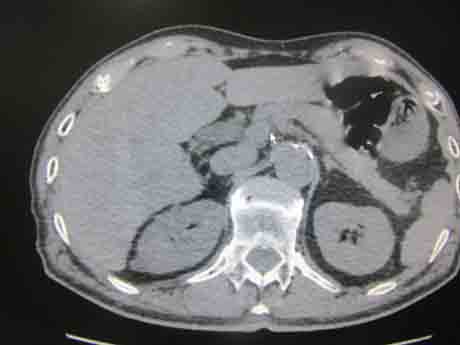

CT50526:肝脏钙化诊断什么病?

肝脏钙化诊断什么病?

考虑肝右叶感染性病变后遗改变。

肝包虫钙化?碘油栓塞治疗后?建议强化和结合临床病史

包虫病

包虫钙化可能

支持大家,但肝脏占位碘油栓塞可能性大

建议强化观察内部改变

除考虑上述可能疾病外,还应排除是否进行肝脏肿瘤碘化油栓塞治疗。